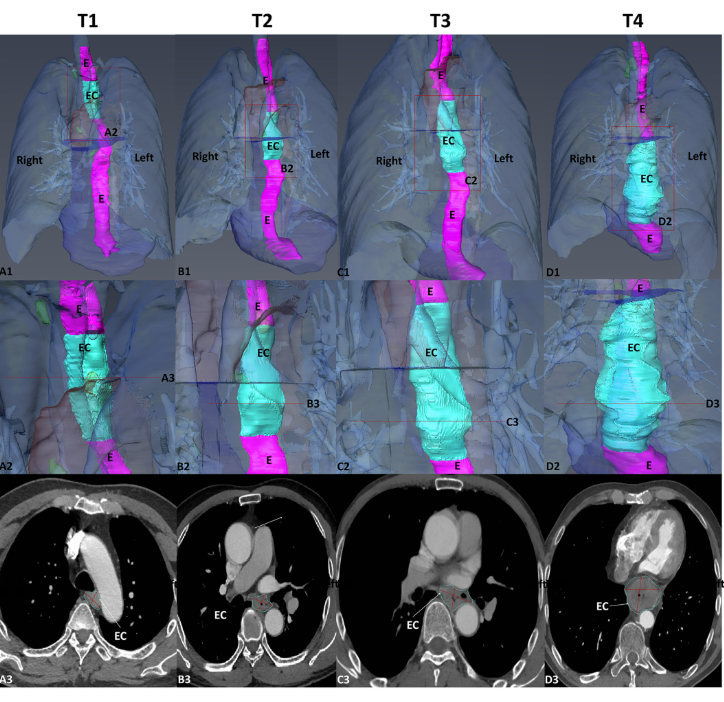

Pre-operative CTA images of 155 patients with EC were retrospectively collected and divided into four groups: T1–T4. We used Amira software to segment and 3D reconstruct the EC, oesophagus, aorta, pericardium and peripheral lymph nodes and measured their surface area, volume, major axis, minor axis, longitudinal length, roughness and relationship to the aorta of the EC. One-way ANOVA, independent sample t-test, ROC, etc., were performed and critical values between different T-stages were calculated. We also invited two radiologists to evaluate the measurements.

We used Amira software to segment and 3D reconstruct the EC, oesophagus, aorta, pericardium and peripheral lymph nodes and measured their surface area, volume, major axis, minor axis, longitudinal length, roughness and relationship to the aorta of the EC. […] To obtain a 3D reconstructed model of the EC for further analytical studies, thin-CTA images of 1–2 mm thickness exported from the workstation in DICOM format were uploaded to Amira software (v.6.0.0) for manual segmentation of the EC images. […], Once image segmentation is complete, the original and segmented images were saved separately in “.am” format. 3D models were reconstructed using the Generate Surface in Amira software, which allows a 3D model of EC to be viewed in all directions, moved, scaled and rotated […],  In the 3D EC reconstruction models, the surface area volume module in Amira software was used to measure the surface area and volume of the tumour and surrounding normal tissue and to analyse the volume relationships between tumour and total oesophageal at different T-stages. […]